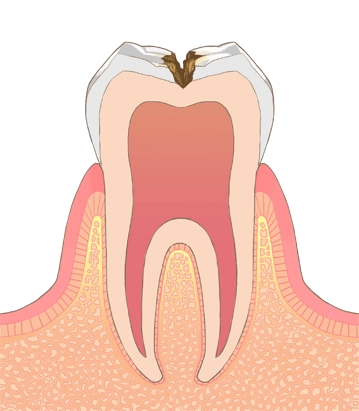

C0

歯の前兆

歯の表面からカルシウムなどの

無機成分が溶け始めます。

C1

軽度の虫歯

表面のエナメル質が溶け始めます。まだ痛みはありません。

C2

中度の虫歯

むし歯が進行し、象牙質に達します。冷たい物・甘い物などが染みてきます。

C3

重度の虫歯

歯の神経までむし歯が達します。ズキズキとした痛みがひどくなってきます。

C4

最重度の虫歯

歯全体がむし歯に侵され、歯根だけが残ります。神経が死んで、歯根に膿が溜まります。